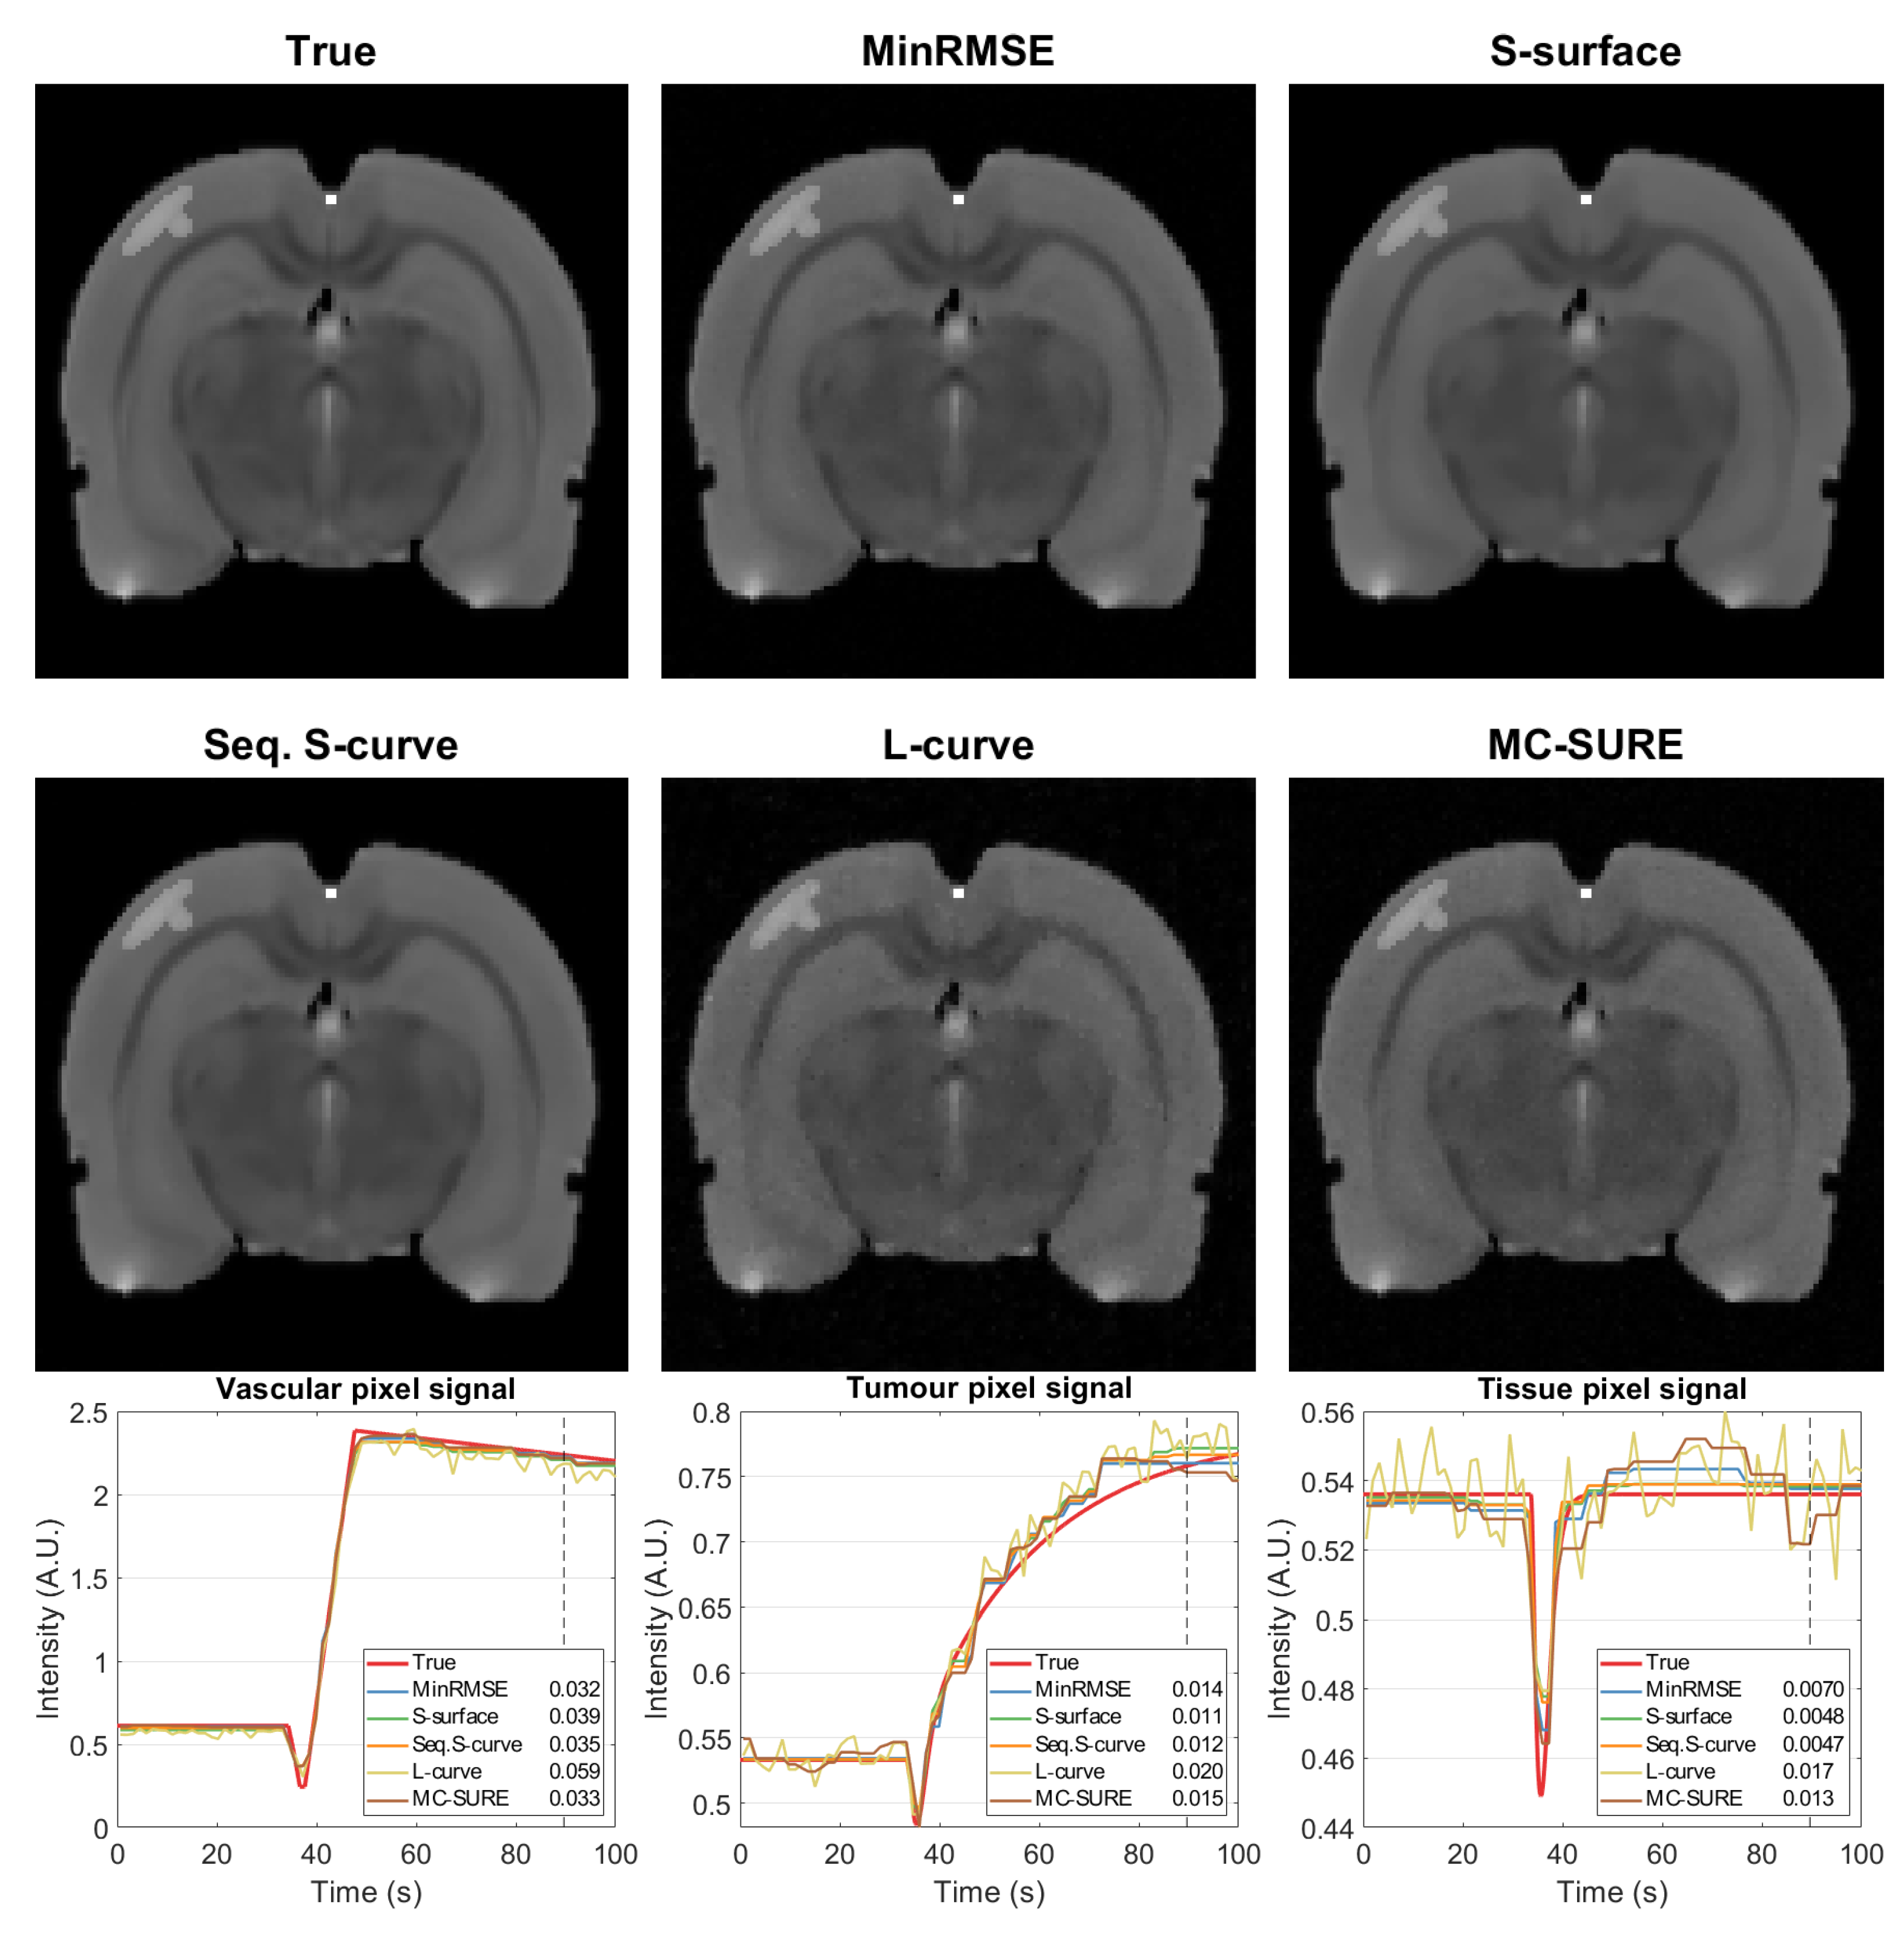

4.1. Simulated Data

4.2. Experimental Data